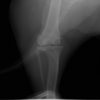

術前写真

手術前後のTPA(脛骨高平部の角度)を測定しています。

約29°から約10°へ矯正されています。